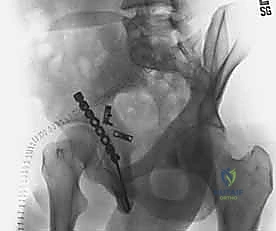

5. التثبيت الداخلي (Internal Fixation)

بعد التأكد من الرد المثالي باستخدام الأشعة داخل العمليات، يتم تثبيت الكسر بشكل نهائي.

* يتم استخدام مسامير معدنية (Screws) لتثبيت الشظايا الكبيرة.

* يتم وضع شرائح معدنية داعمة (Reconstruction Plates) على طول الجدار الخلفي والعمود الخلفي لتوفير دعم ميكانيكي قوي يمنع انزلاق الشظايا ويتحمل الضغط. يتم تشكيل هذه الشرائح يدوياً أثناء العملية لتطابق الانحناءات الطبيعية لحوض المريض.

* في بعض الحالات، تُستخدم تقنية "الشرائح الزنبركية" (Spring plates) لتثبيت الشظايا الصغيرة جداً التي لا يمكن وضع مسامير فيها.

6. إصلاح الأنسجة الرخوة والإغلاق